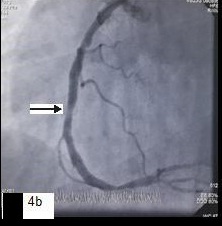

Five patients (12.5 %) had normal angiograms [Table/Fig-2,2b,3,3b], six (15%) had non-significant disease [Table/Fig-4,4b,5a,5b] and 29 patients (72.5%, 26 male & 3 female) had significant disease [Table/Fig-6a,6b],[7a,7band8] on CT coronary angiography, which was also proved on invasive angiography [Table/Fig-9]. The incidence of significant coronary detected was highest in age group of 41-60 years [Table/Fig-10].

Curved reformatted image,

Catheter angiography image showing non-significant stenosis in mid RCA